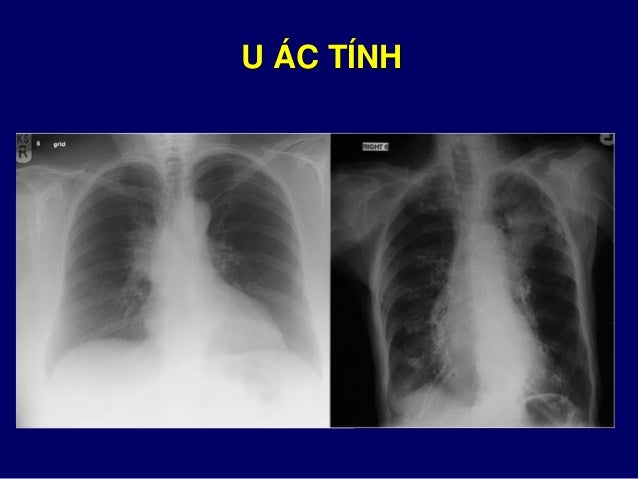

73. 73. XẸP THÙY TRÊN PHỔI TRÁI

90. 90. ĐẶC ĐIỂM KHỐI U CẦN MÔ TẢ  Vị trí: quanh rốn và thùy trên phổi  Kích thước: to/nhỏ, thay đổi so phim cũ  Bờ nham nhở hay đều  Trong khối u: Calci hóa, hang hóa  Kèm bất thường: hạch, hủy xương sườn

91. 91. ĐẶC ĐIỂM KHỐI U CẦN MÔ TẢ